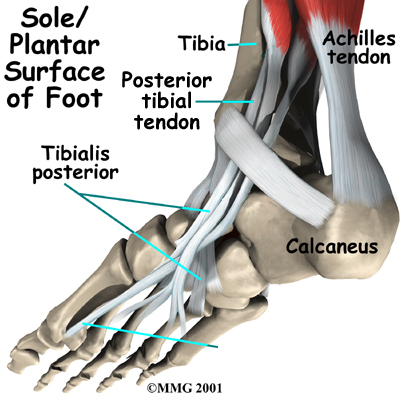

Anatomy

Where is the posterior tibial tendon, and what does it do?

The posterior tibial tendon runs behind the inside bump on the ankle (the medial malleolus), across the instep, and into the bottom of the foot. The tendon is important in supporting the arch of the foot and helps turn the foot inward during walking.